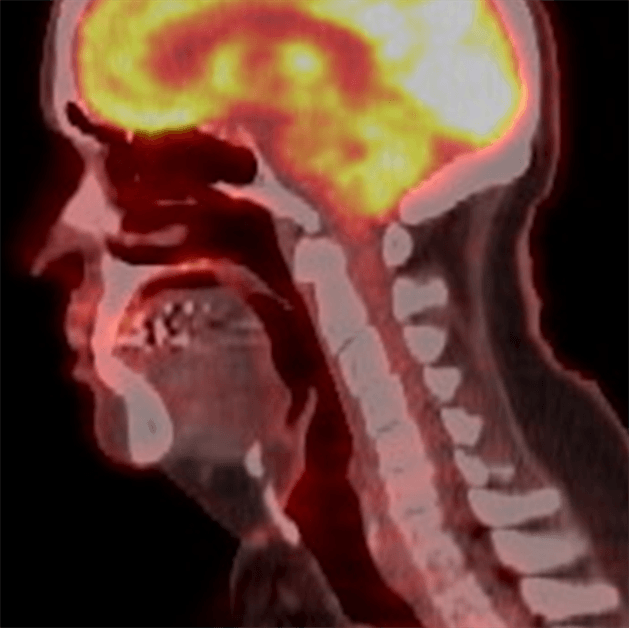

Reporting Head and Neck Cancer

Head and neck cancer is the 8th most common cancer in the UK, with around 12,400 new cases diagnosed per year (2016-2018). Head and neck cancer incidence rates are projected to rise by 3% in the UK between 2023-2025 and 2038-2040 (Cancer Research UK).

At our institution, head and neck cancer accounts for 8% of all PET-CT scans performed.

The evidence-based indications for use of PET-CT in the UK 2016 list five indications for FDG PET-CT in head and neck cancer: